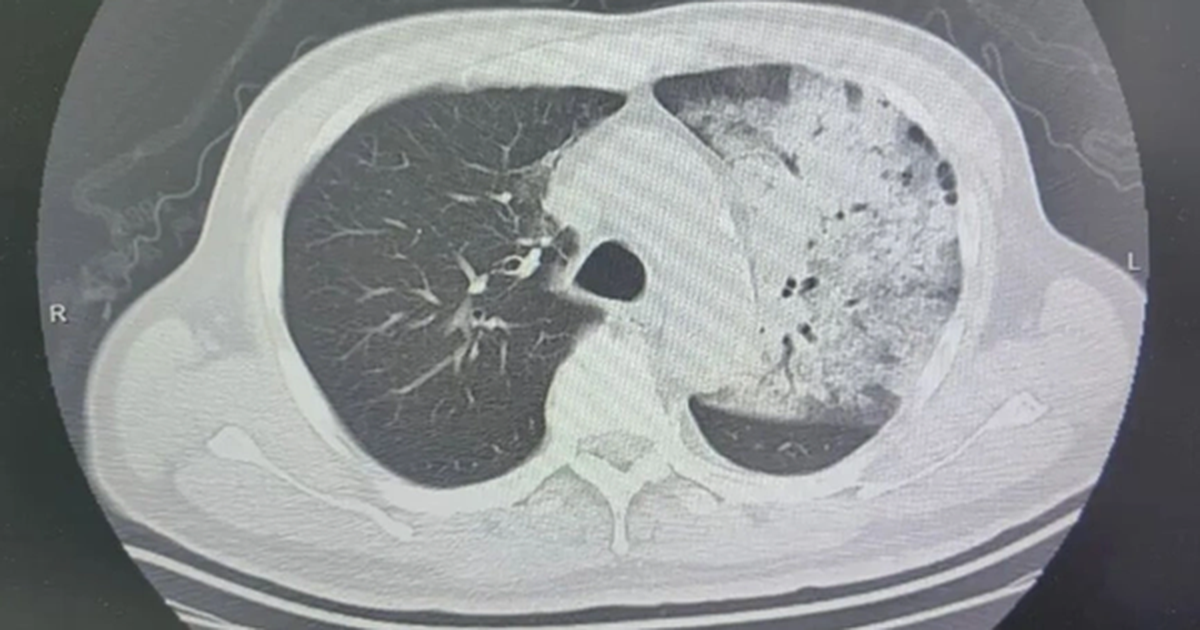

Sau một tuần điều trị tại bệnh viện địa phương, tình trạng của ông xấu đi đột ngột. Khó thở, rối loạn ý thức cùng kết quả chụp CT cho thấy hai phổi bị nhiễm trùng nặng, gần như “trắng xóa”. Dù đã được hỗ trợ thở máy, tình trạng oxy máu vẫn không cải thiện.